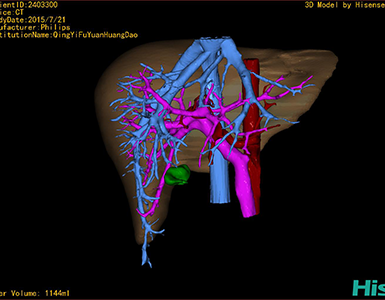

术前三维重建及手术方案设计:

将0.625mm双源薄层CT资料的静脉期和动脉期Dicom格式文件导入海信CAS系统。

通过调节窗宽窗位调整CT序号,对肿瘤,肝实质,胆囊,下腔静脉,肿瘤,肝动脉、门静脉及肝静脉等进行三维重建;系统自动计算肿瘤体积和肝脏体积。

模拟手术操作,自动计算切除肿瘤体积。肝脏体积为1096ml,胰腺肿瘤体积为115.5ml,通过比对12-13岁正常肝脏体积为1116.86±158.78 ml,通过术前模拟手术,精准判断切除后肝脏体积无明显变化,避免肝衰竭发生。

术前三维重建:

重建图片